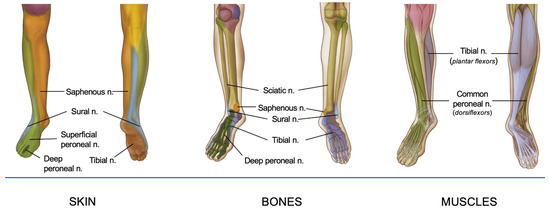

3. Innervation of the Foot and Ankle

The sensory and motor innervation of the foot and ankle is primarily derived from the sciatic and saphenous nerves, branches of the lumbosacral plexus. The sciatic nerve (roots L4-S3) descends through the posterior thigh and bifurcates in the popliteal fossa into the tibial and common peroneal nerves [7]. The tibial nerve descends and passes posterior to the medial malleolus before branching into medial and lateral plantar nerves. The plantar nerves provide sensory innervation to the sole of the foot, and the intrinsic muscles of the foot (e.g., flexor digitorum brevis and abductor hallucis). Specifically, the medial plantar nerve innervates the medial two-thirds of the sole of the foot, and the lateral plantar nerve innervates the lateral third and the small muscles of the foot [2]. The common peroneal nerve wraps around the fibular neck after branching from the sciatic nerve and then derives into the deep peroneal nerve (DPN) and superficial peroneal nerve (SPN). DPN is responsible for motor innervation to the muscles of the anterior compartment of the leg (e.g., tibialis anterior) and sensory innervation to the interdigital space between the first and second toes. SPN provides sensation to the dorsum of the foot and the lateral part of the lower leg and provides motor innervation to the peroneus longus and brevis muscles. The medial side of the foot and ankle are also innervated by the saphenous nerve (sensory branch of the femoral nerve), which is the longest branch of the femoral nerve running along the great saphenous vein. It provides cutaneous sensation to the medial leg, ankle and foot. A comprehensive understanding of this intricate anatomy is essential for effective regional anesthesia, as it allows precise targeting of the nerves responsible for sensory and motor function in the surgical area, optimizing perioperative pain management.

Innervation of foot and ankle is resumed in Figure 1.

A synthesis of foot and ankle innervation, organized by cutaneous, muscular, and bony structures.